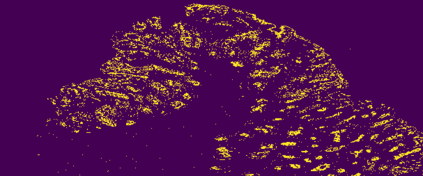

The usage of chemical imaging technologies is becoming a routine accompaniment to traditional methods in pathology. Significant technological advances have developed these next generation techniques to provide rich, spatially resolved, multidimensional chemical images. The rise of digital pathology has significantly enhanced the synergy of these imaging modalities with optical microscopy and immunohistochemistry, enhancing our understanding of the biological mechanisms and progression of diseases. Techniques such as imaging mass cytometry provide labelled multidimensional (multiplex) images of specific components used in conjunction with digital pathology techniques. These powerful techniques generate a wealth of high dimensional data that create significant challenges in data analysis. Unsupervised methods such as clustering are an attractive way to analyse these data, however, they require the selection of parameters such as the number of clusters. Here we propose a methodology to estimate the number of clusters in an automatic data-driven manner using a deep sparse autoencoder to embed the data into a lower dimensional space. We compute the density of regions in the embedded space, the majority of which are empty, enabling the high density regions to be detected as outliers and provide an estimate for the number of clusters. This framework provides a fully unsupervised and data-driven method to analyse multidimensional data. In this work we demonstrate our method using 45 multiplex imaging mass cytometry datasets. Moreover, our model is trained using only one of the datasets and the learned embedding is applied to the remaining 44 images providing an efficient process for data analysis. Finally, we demonstrate the high computational efficiency of our method which is two orders of magnitude faster than estimating via computing the sum squared distances as a function of cluster number.